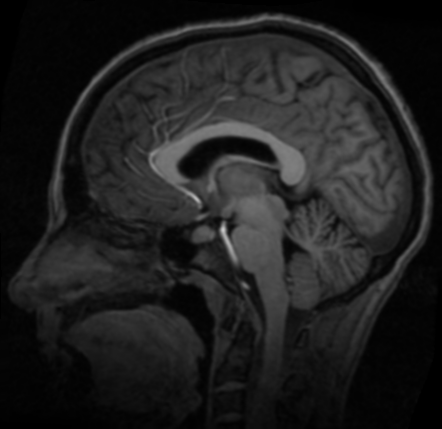

使用以上实现的配准方法,对脑部图像进行配准。

浮动图像

配准图像